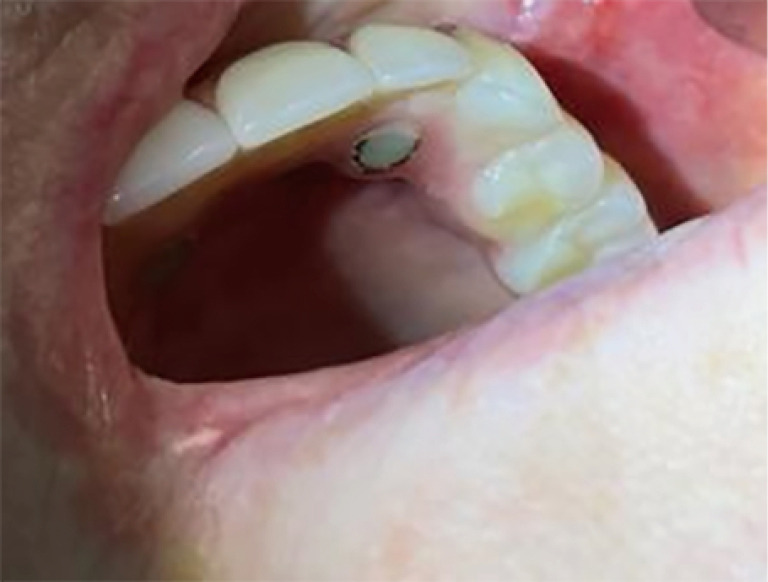

Case description: A 60-year-old female with IOBCC was first diagnosed in August 2016 involving right buccal mucosa and right anterior hard palate. She subsequently underwent wide local excision with involved margins. Her first local recurrence occurred four and a half years after initial diagnosis and went on to have further surgical resection. Her second local recurrence occurred 2 years later, where further surgery and radiotherapy were not amenable. She was then treated with vismodegib 150 mg daily, delivered via her gastrotomy feeding tube and she achieved clinical complete response within 3 months of treatment. Following 6 months of treatment, due to progressive side effects, she ceased treatment. She remains on surveillance and disease-free on clinical examination and repeat biopsy for the past 2 years. To our knowledge, this is the first case of inoperable recurrent IOBCC treated with vismodegib, delivered via gastrotomy tube, leading to a durable complete response. The patient's tumour showed significant regression within 3 months of treatment initiation, with continued improvement over the following year. The rapid and durable response to vismodegib in this case is particularly noteworthy, considering the aggressive nature of recurrent IOBCC and the patient's prior treatment history. The effective administration of vismodegib through a gastrostomy feeding tube is an additional important clinical finding. This approach demonstrates the flexibility of vismodegib treatment and may be applicable to other patients facing feeding or medication administration challenges.

Conclusions: Vismodegib can induce rapid, effective, and durable responses in IOBCC. The administration of vismodegib via gastrotomy tube was found to be safe and did not compromise its efficacy. Longer-term and larger cohort follow-up studies are needed to fully evaluate the efficacy and safety of vismodegib in this patient population.